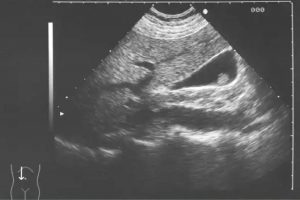

El programa fue diseñado para llevar de la mano al participante y ofrecerle herramientas que le permitan hacer una evaluación radiológica atinada, lo cual lo llevará a un diagnóstico que por ende arrojará el tratamiento idóneo. El énfasis se ha dado en la metodología diagnóstica, que es por inducción, así como el manejo del paciente, para crear una conciencia responsable y humana entre los que se dedican o quieren iniciarse en la práctica de la ultrasonografía. Dado a que existe una aplastante demanda de estudios de ultrasonido ante el insuficiente número de médicos radiólogos certificados, además de que el servicio de rayos x en México ha sufrido de ineficiencia en la aplicación del estudio y elaboración diagnóstica de la patología, la labor de este curso es formar de manera profesional a los médicos para que cubran y aminore en gran medida este problema que habita en el sector de salud.